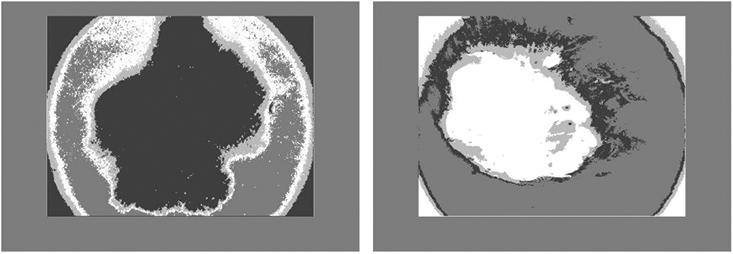

In this paper, the utilization of the watershed algorithm is initiated by modifying the RGB images into grayscale. Consequently, to provide a smooth image, a morphological top-hat filter is utilized. In the next step, the images are transformed into binary format employing grayscale and are later complemented. In the next step, the distance is computed and the watershed transformation is calculated. The segmented regions are displayed by employing distinct colors. Fig. 8 illustrates skin cancer images after applying the watershed segmentation approach.

Figure 8: Illustration of skin cancer images after applying the watershed segmentation approach